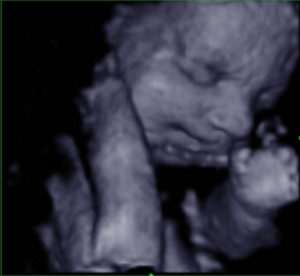

If you are an expected mother and anxious to get a glimpse of your new creation, 3D4D Imaging Center can make it happen. You will be able to see activities of your baby inside the womb which is difficult or impossible to identify with traditional scanning.

Baby Faces 2

30 Weeks – Term

Includes 10-14 pics in 3D, watching the baby move (4D), confirmation of gender. 30 minute session.